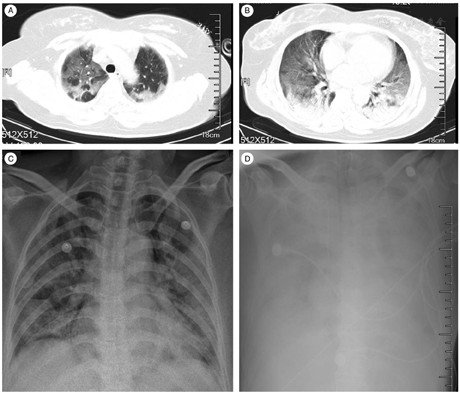

The clinical features and laboratory test results of the five patients are summarized in Table 2. Fever, cough, and dyspnea were the most common symptoms. The white blood cell counts varied among these patients, but the lymphocyte counts were generally low. The alanine aminotransferase and serum creatine levels were normal or only slightly increased. Bilateral ground-glass opacities and consolidation were observed on chest radiography from two representative patients, Patient 2 based on aortic arch scan [Figure 4A] and pulmonary vein scan [Figure 4B] on day 10 after symptoms onset and Patient 5 taken on day 12 [Figure 4C] and 13 [Figure 4D] after symptoms onset. Several complications were observed in these patients. Four of the five patients (except for Patient 3) developed acute respiratory distress syndrome requiring oxygen therapy, and two patients were given extracorporeal membrane oxygenation. Two patients (Patients 1 and 5) experienced secondary infections, and Patient 5 later developed septic shock as well as acute kidney injury, and ultimately died of multi-organ failure. Patient 3 was discharged on January 8, 2020 (day 17 after symptoms onset). The other three patients were still hospitalized at the time of manuscript preparation. The treatments for these patients were shown in Table 1.